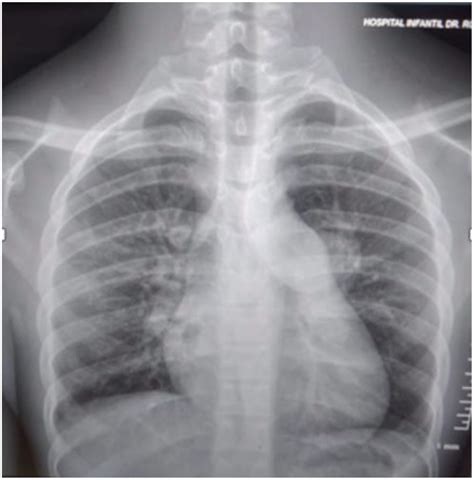

Key findings on a Pulmonary Embolism X Ray that may suggest PE include:

• Wedge-shaped opacities: These are areas of increased density in the lung tissue, often seen in the periphery of the lung.

• Pleural effusion: Fluid accumulation in the pleural space, which can be a sign of inflammation or infection.

• Enlarged pulmonary arteries: Dilatation of the pulmonary arteries, which may indicate increased pressure due to a clot.

• Atelectasis: Collapse or incomplete expansion of the lung tissue, which can be a sign of obstruction.

However, it is important to note that these findings are not specific to PE and can be seen in other conditions. Therefore, further diagnostic testing is often required to confirm the diagnosis.